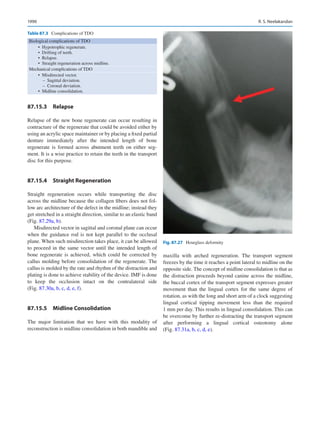

three fundamental principles—patient care, education, and

meaningful research, we will continue to justify our exis-

tence in the future.

References

1.	Suśruta Samhita. English translation by Kaviraj Kunja Lal

Bhishagratna, Calcutta, 1907, Chapter 16, 152–154.